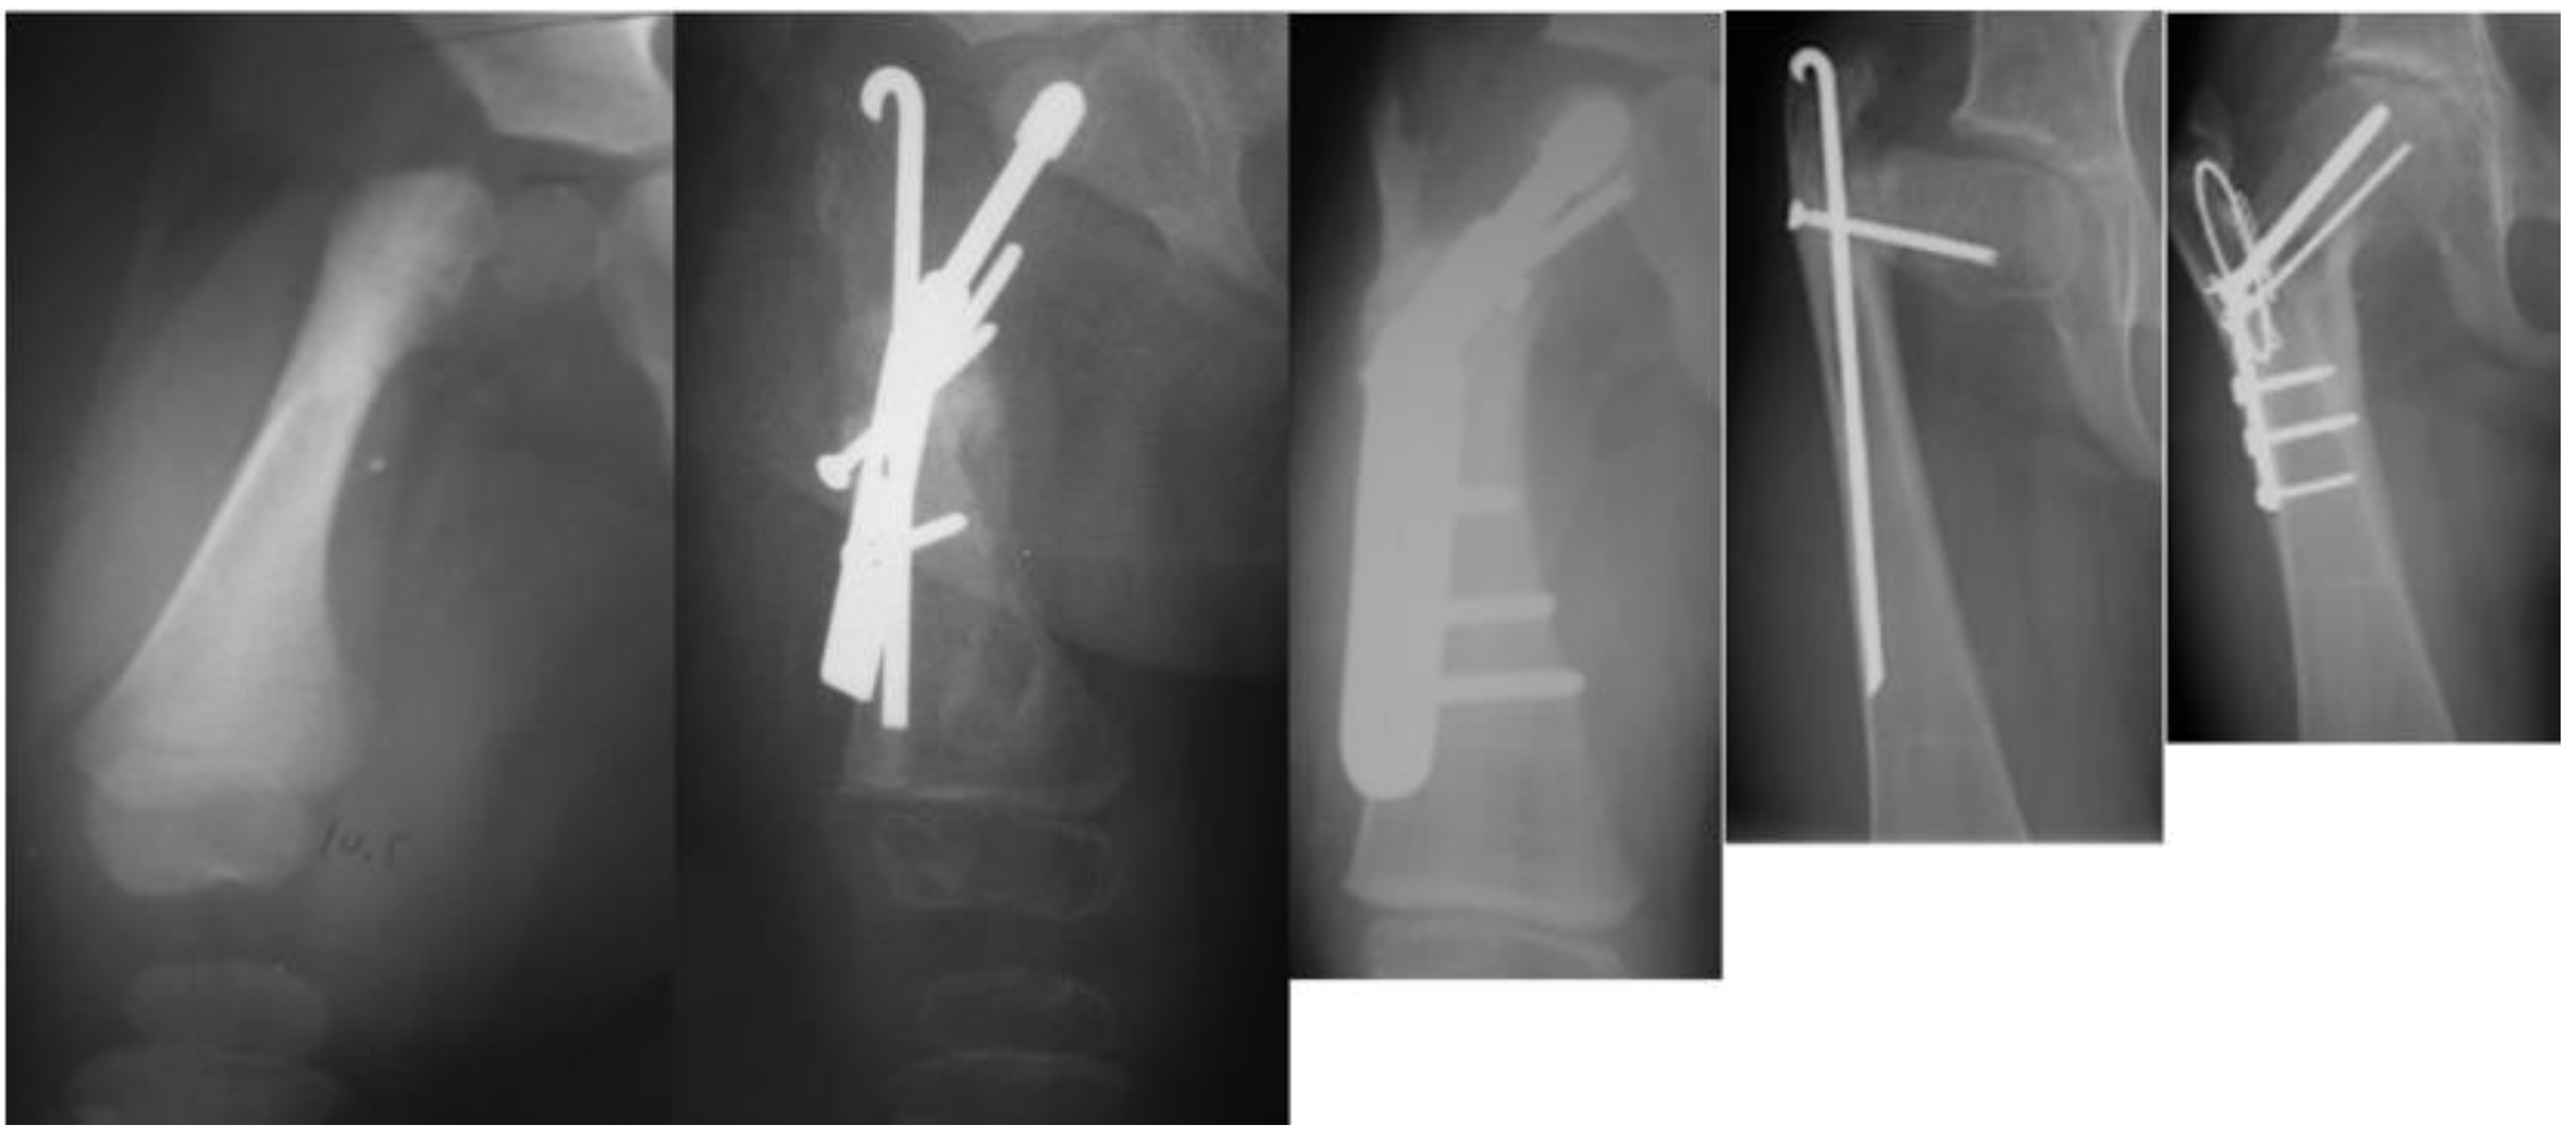

Figure 5.

Radiographs showing: preoperative type 1b CFD (leftmost); after SUPERhip procedure fixed with infant sliding hip screw (second to left); the neck did not ossify so the infant sliding hip screw was changed to a larger size sliding hip screw (revision SH) a year later (middle); delayed ossification of the neck persisted and two years later the hip screw was removed and recurrent varus deformity occurred (second to right); a second revision SH was performed with blade plate fixation and insertion of BMP2 and the neck fully ossified (rightmost).